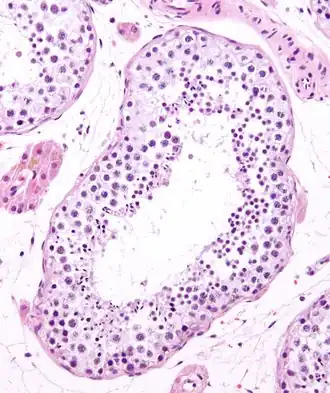

Seminiferous tubule (transverse section).

Photomicrograph of section through rat testis, showing seminiferous tubules.